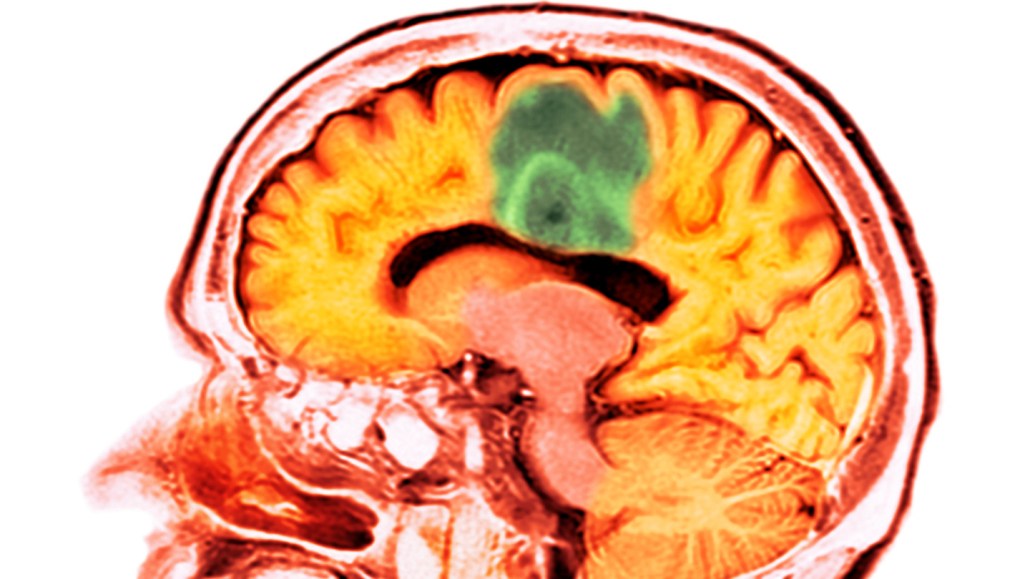

Glioblastoma (green in this CT scan) is a type of brain cancer that is difficult to treat. A study shows how pairing ultrasound with microbubbles temporarily opens the brain’s protective barrier, allowing a chemotherapy drug to enter the organ.

DR P. MARAZZI/SCIENCE PHOTO LIBRARY/Getty Images